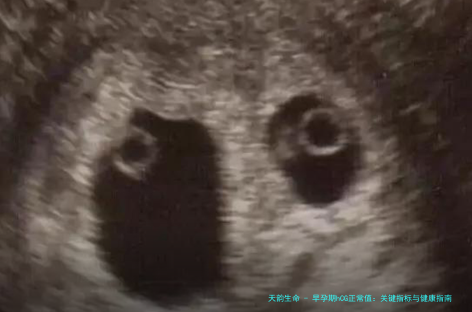

hCG值受多种因素影响,比如多胎妊娠——怀双胞胎或三胞胎时,hCG水平往往更高,可能超过单胎的正常上限。另一方面,如果hCG值异常低或上升缓慢,可能提示宫外孕或流产风险。近5年的数据显示,约10-15%的早孕异常与hCG波动有关。我的一位患者就曾因hCG值持续不升,被诊断为宫外孕,幸好及早发现并处理了。此外,母亲的年龄、体重甚至吸烟习惯,也可能轻微影响hCG水平。因此,解读hCG值时,不能孤立看待,要结合B超和其他症状综合判断。